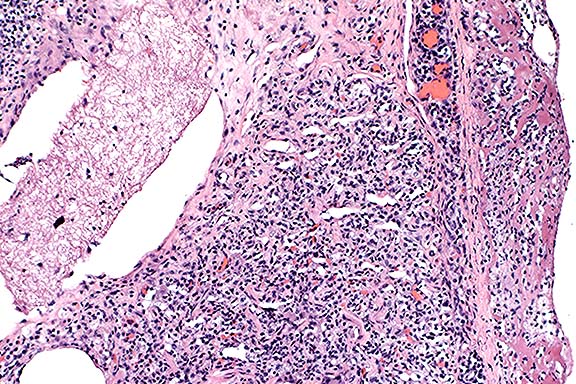

Contributor's Diagnosis and Comments: Ovotestis.

Chromosomal sex is normally determined at fertilization by the formation of either an XY or XX zygote. The Tdy gene on the Y chromosome encodes the protein testis-determining factor, which initiates testicular differentiation. Studies in mice have shown Tdy to be the only Y-linked gene necessary for testicular differentiation. Male phenotypic sexual determination results from the testicular secretion of 1) Müllerian inhibiting substance (MIS), which causes the Müllerian duct system to regress, and 2) testosterone, which promotes development of the vas deferens and epididymides from the Wolffian ducts. In the absence of the Y chromosome and Tdy gene, the default pathway to female gonadal sexual differentiation is initiated.

Hermaphrodites are classified according to the morphology of

the gonads present. A true hermaphrodite has at least one gonad

containing ovarian and testicular tissue (i.e. an ovotestis) or

has one male and one female gonad. A pseudohermaphrodite has gonads

of one sex and accessory reproductive organs of the opposite sex.

A male pseudohermaphrodite has testes and female accessory sex

organs; a female pseudohermaphrodite has ovaries and male accessory

reproductive organs.